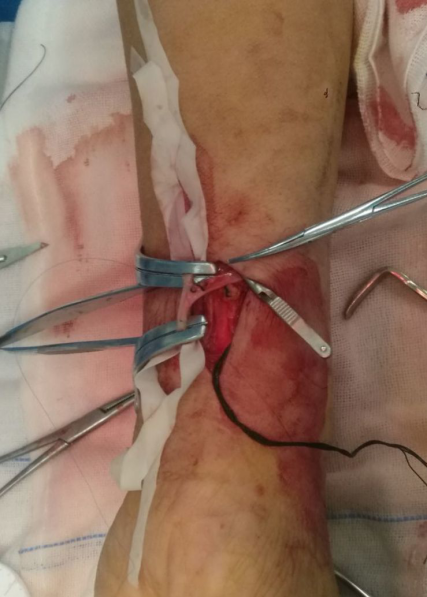

尺动脉和贵要静脉吻合成功